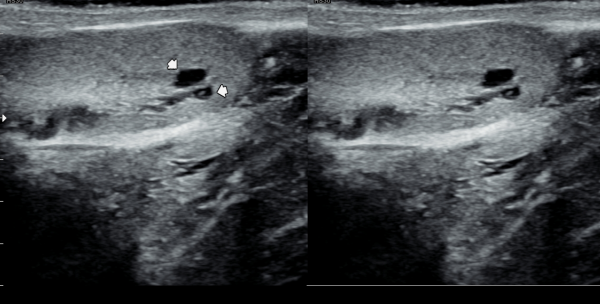

5년전부터 폐암으로 투병중 전립선 치료를 받지 못하던중 최근 하복부 통증이 심해져 내원 당일 추적 경직장 전립선 초음파 추적 검사상

전립선 낭종들이 커지고 사정관 입구의 미세 결석이 관찰되는 사진입니다.

A follow-up transrectal prostate ultrasound image taken on the day of the visit shows enlargement of prostatic cysts and microcalcifications at the opening of the ejaculatory duct in a patient who had been unable to receive prostate treatment due to lung cancer for the past five years and recently developed worsening lower abdominal pain.